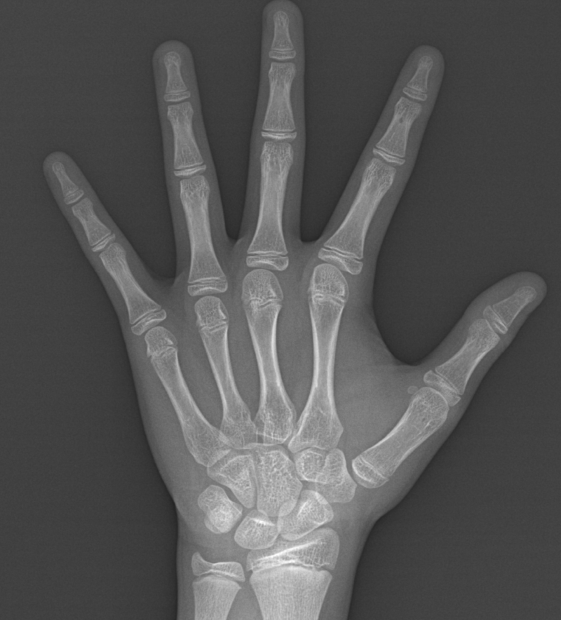

성장판 사진. 환아의 역연령 (실제 나이)는 만 10세 10개월이다. 뼈나이는 몇살일까?

"어머님, 지금 뼈나이는 12살~12살 6개월 정도 되어 보여요. 자기 나이보다 1년 반정도 빠른 거예요.

그리고 작년 7월 초에 진료 보면서 측정했던 키랑 비교하면, 지금 10개월 동안 143.2 -> 150.5cm,

7.3cm 컸어요. 1년으로 환산하면 1년 동안 8.8cm 컸습니다. 여자 아이들에게서 이 정도면 지금 급성장기에 돌입한 거고, 앞으로 급성장기는 6개월 정도 남았어요. 그 뒤로는 이미 초경을 한 상태이기 때문에 키 크는 속도는 현저히 줄어들 겁니다."